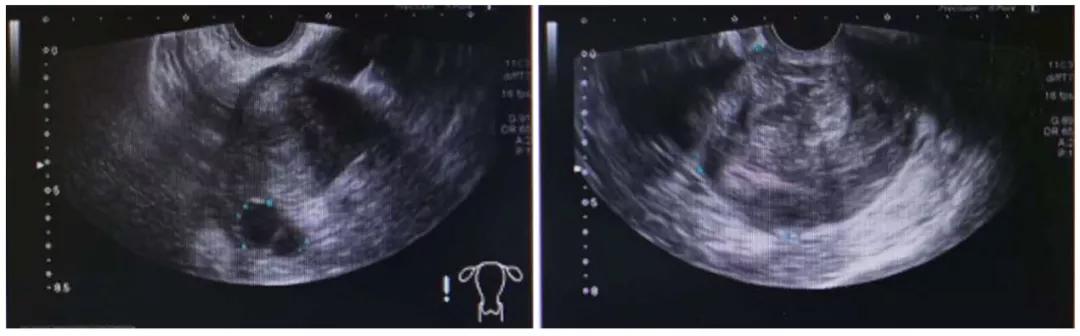

入院妇科超声:子宫前位,宫体正常大,内膜厚1.0cm(双层),宫 区见 多个低回声,较大位于宫颈后唇7×6.9×6.4cm,内部回声不均,边界清。右卵巢内见2.5×2.2×1.8cm囊性块,见分隔,内液清。左附件区未见明显包块。诊断结果:子宫多发肌瘤(较大一个宫颈肌瘤伴变性可能),右卵巢内囊性块。